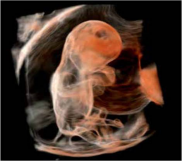

1. 容积成像

* 琥珀成像Shadow Glass (包括组织成像和血流成像两种模式):半透明成像效果,兼容所有彩色模式,可结合组织和血管信息,易于病灶判断。

* Luminance点光源仿真模式:可移动虚拟光源,分辨率进一步提升,响应时间快,支持4D&Smart sensor 3D